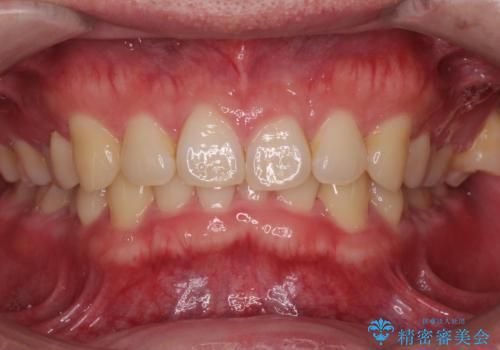

下の歯のがたつきが気になる。 インビザラン&ワイヤー部分矯正併用

- 下の歯が気になるとの事で来院。

左上の奥歯がシザーバイトがありワイヤーで部分的な矯正を行い、シザーバイトを改善した後にインビザラインで全体的な矯正治療を行いました。

シザーバイトは歯と歯が噛み合っていないのでしっかり噛むように処置をする必要があります。

歯のがたつきが改善され大変満足されました。